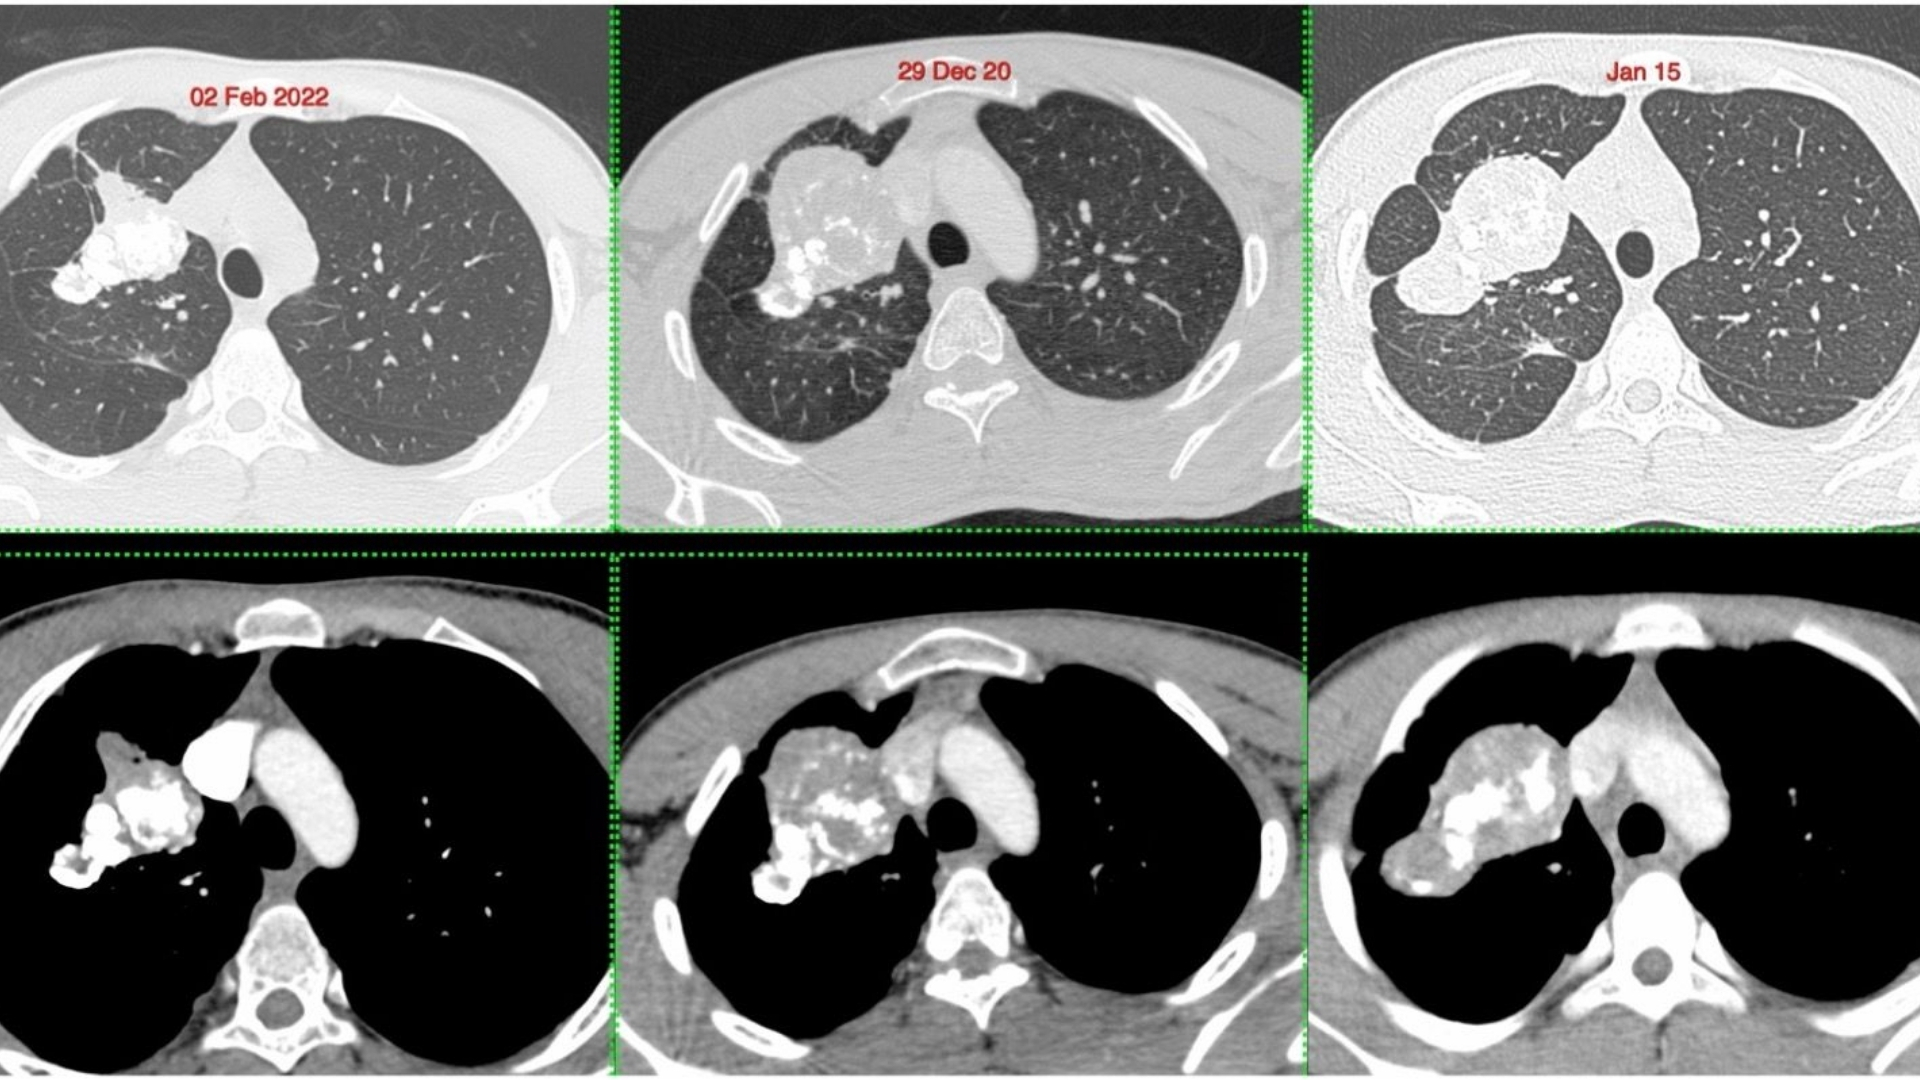

準確的分期對肺發炎性肌纖維母細胞腫瘤患者的臨床管理和預後有重大影響。分期評估腫瘤的大小、位置、轉移擴散和全身受累情況。香港和亞洲地區的研究顯示,基於可用的醫療基礎設施和診斷能力,患者的表現、治療方法和存活率均有所不同。

• 進階診斷:最先進的影像(例如 PET-CT、Siemens MRI)和分子剖析,以找出腫瘤的代謝漏洞。

• 醫療記錄:最近的診斷報告、影像掃描(如 CT、MRI、PET-CT)、病理結果和治療史。接受數位或實體複本。